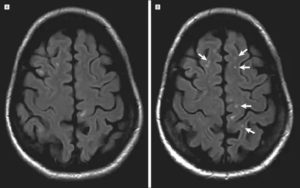

Справочно. Лучше всего визуализируются очаги глиоза на МРТ либо КТ-аппаратах.

Эти современные приборы позволяют с высокой точностью выявить сосудистые изменения, опухолевые процессы, патологические участки в белом веществе лобных долей, очаги кровоизлияний, ишемическое поражение.

Диагностика глиоза головного мозга основывается на данных КТ и МРТ:

- Магнитно-резонансная томография, является приоритетным методом для выявления таких отклонений. Помощью этого метода, специалист увидит очаги глиоза в мозге, выяснит степень распространенности и определит точную причину возникновения болезни.

- В случае глиоза, обычно в заключении МРТ может быть написано – «картина очага глиоза в левой (правой) лобной доли».

- Если очаги множественные, то данная методика выявит все места их локализации и масштабы гибели нейронов.

- Также магнитно-резонансный томограф определит причину возникновения таких очагов.

- Если виновником отмирания нервных клеток стало заболевание сосудистого характера, то в заключении МРТ будет написано – «картина единичного (множественных) очагов глиоза в белом веществе головного мозга – вероятно, сосудистого генеза». Подробнее о сосудистом генезе головного мозга и что это такое читайте в нашей аналогичной статье.